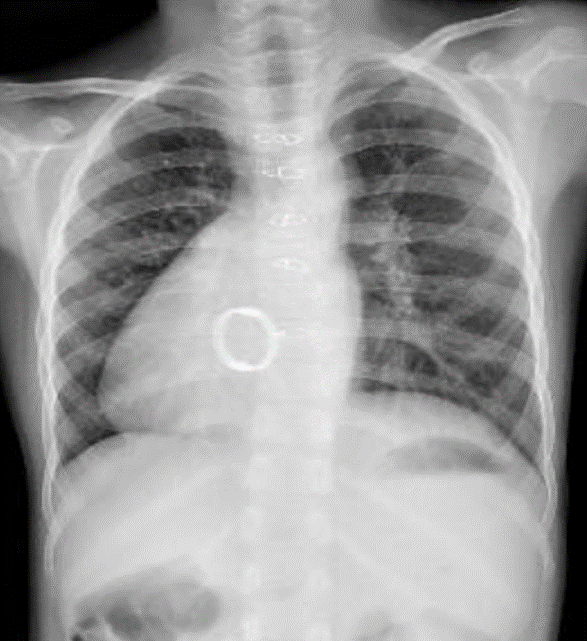

Hãy phân tích tình huống Nữ 30 tuổi Chỉ định: Thay val 2 lá

1-Đảo ngược phủ tạng bóng tim xoay bên (P) lồng ngực 2-Val 2 lá nhân tạo